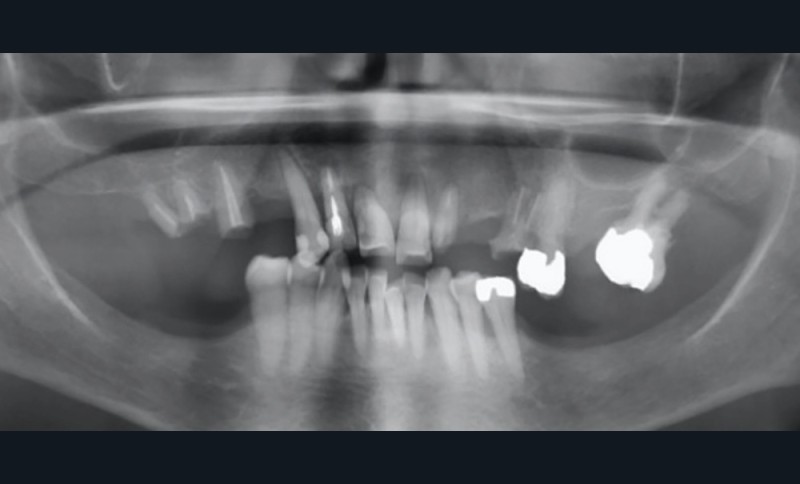

À l’examen endobuccal, le sondage parodontal révèle une parodontite généralisée stade 4 grade A [1] caractérisée par des pertes d’attaches ≥ 5 mm, une alvéolyse au niveau radiographique > 50 % de la hauteur radiculaire, des pertes dentaires en raison de la maladie parodontale et des migrations secondaires dentaires.

Le pronostic dentaire général est mauvais [2], et la conservation des dents résiduelles n’est donc pas retenue (fig. 2).